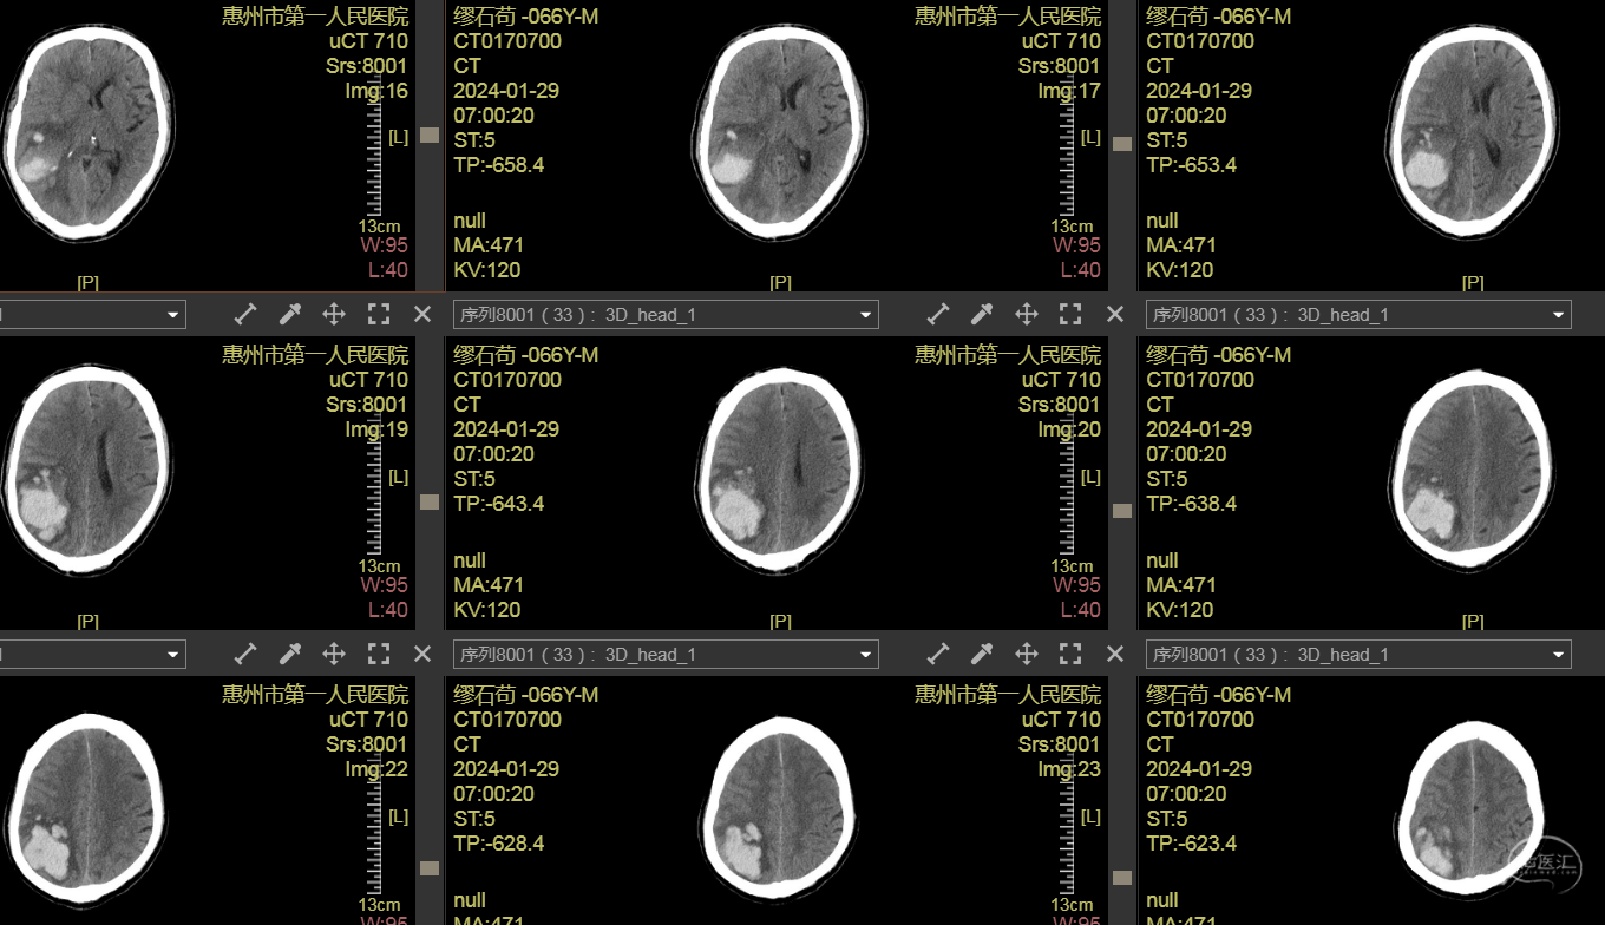

头颅CT示:右侧颞顶枕叶脑出血(78ml),内斑点、小片状持续强化灶,活动性出血?血管畸形?

术前CT

血肿内疑似有血管畸形